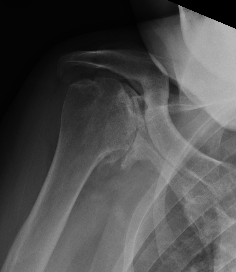

Xray

Template size and fit of glenoid & humeral components